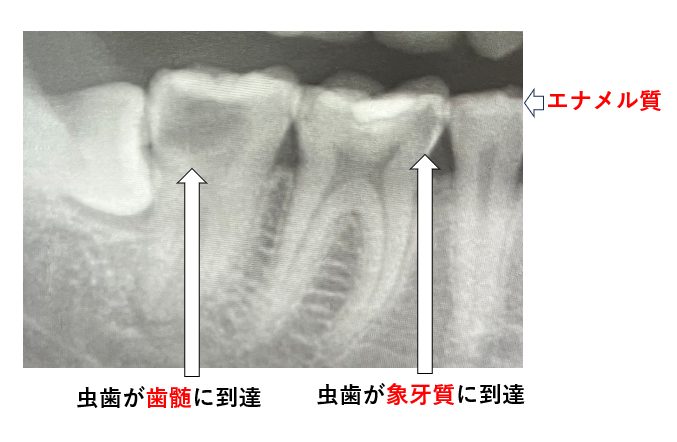

エナメル質を越えて象牙質に達するような深い虫歯や、歯髄組織に達するような痛みを伴う虫歯の治療には麻酔が必要です(図2)。